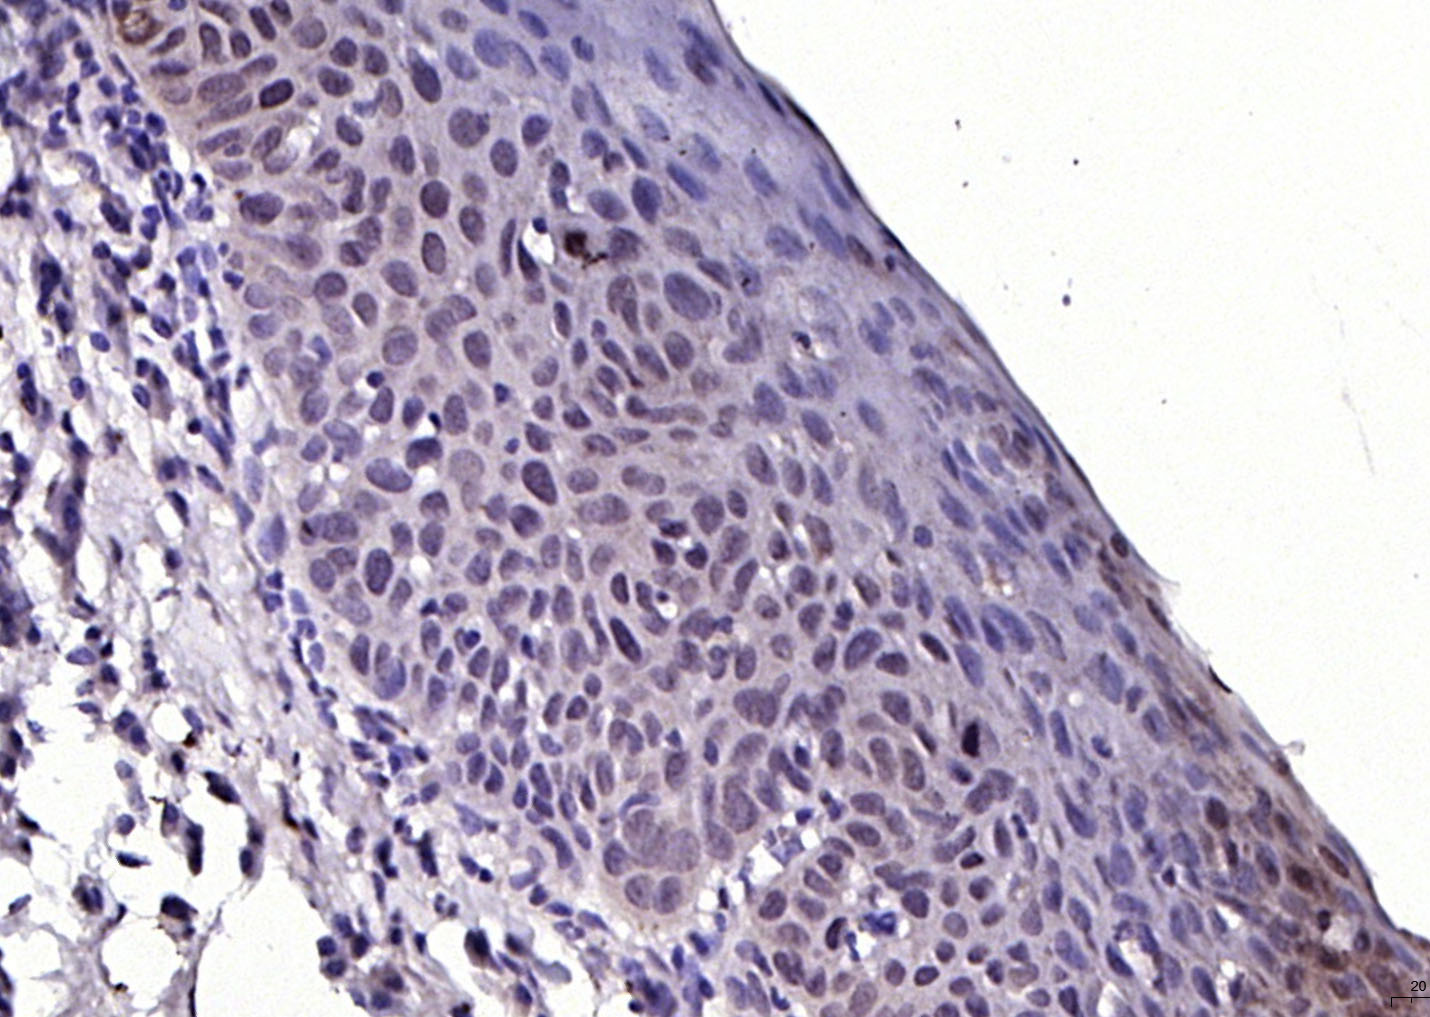

Paraformaldehyde-fixed, paraffin embedded (human meningioma); Antigen retrieval by boiling in sodium citrate buffer (pH6.0) for 15min; Block endogenous peroxidase by 3% hydrogen peroxide for 20 minutes; Blocking buffer (normal goat serum) at 37°C for 30min; Antibody incubation with (FGFR1) Polyclonal Antibody, Unconjugated (bs-0230R) at 1:200 overnight at 4°C, followed by operating according to SP Kit(Rabbit) (sp-0023) instructionsand DAB staining.

Paraformaldehyde-fixed, paraffin embedded (human laryngeal carcinoma); Antigen retrieval by boiling in sodium citrate buffer (pH6.0) for 15min; Block endogenous peroxidase by 3% hydrogen peroxide for 20 minutes; Blocking buffer (normal goat serum) at 37°C for 30min; Antibody incubation with (FGFR1) Polyclonal Antibody, Unconjugated (bs-0230R) at 1:200 overnight at 4°C, followed by operating according to SP Kit(Rabbit) (sp-0023) instructionsand DAB staining.